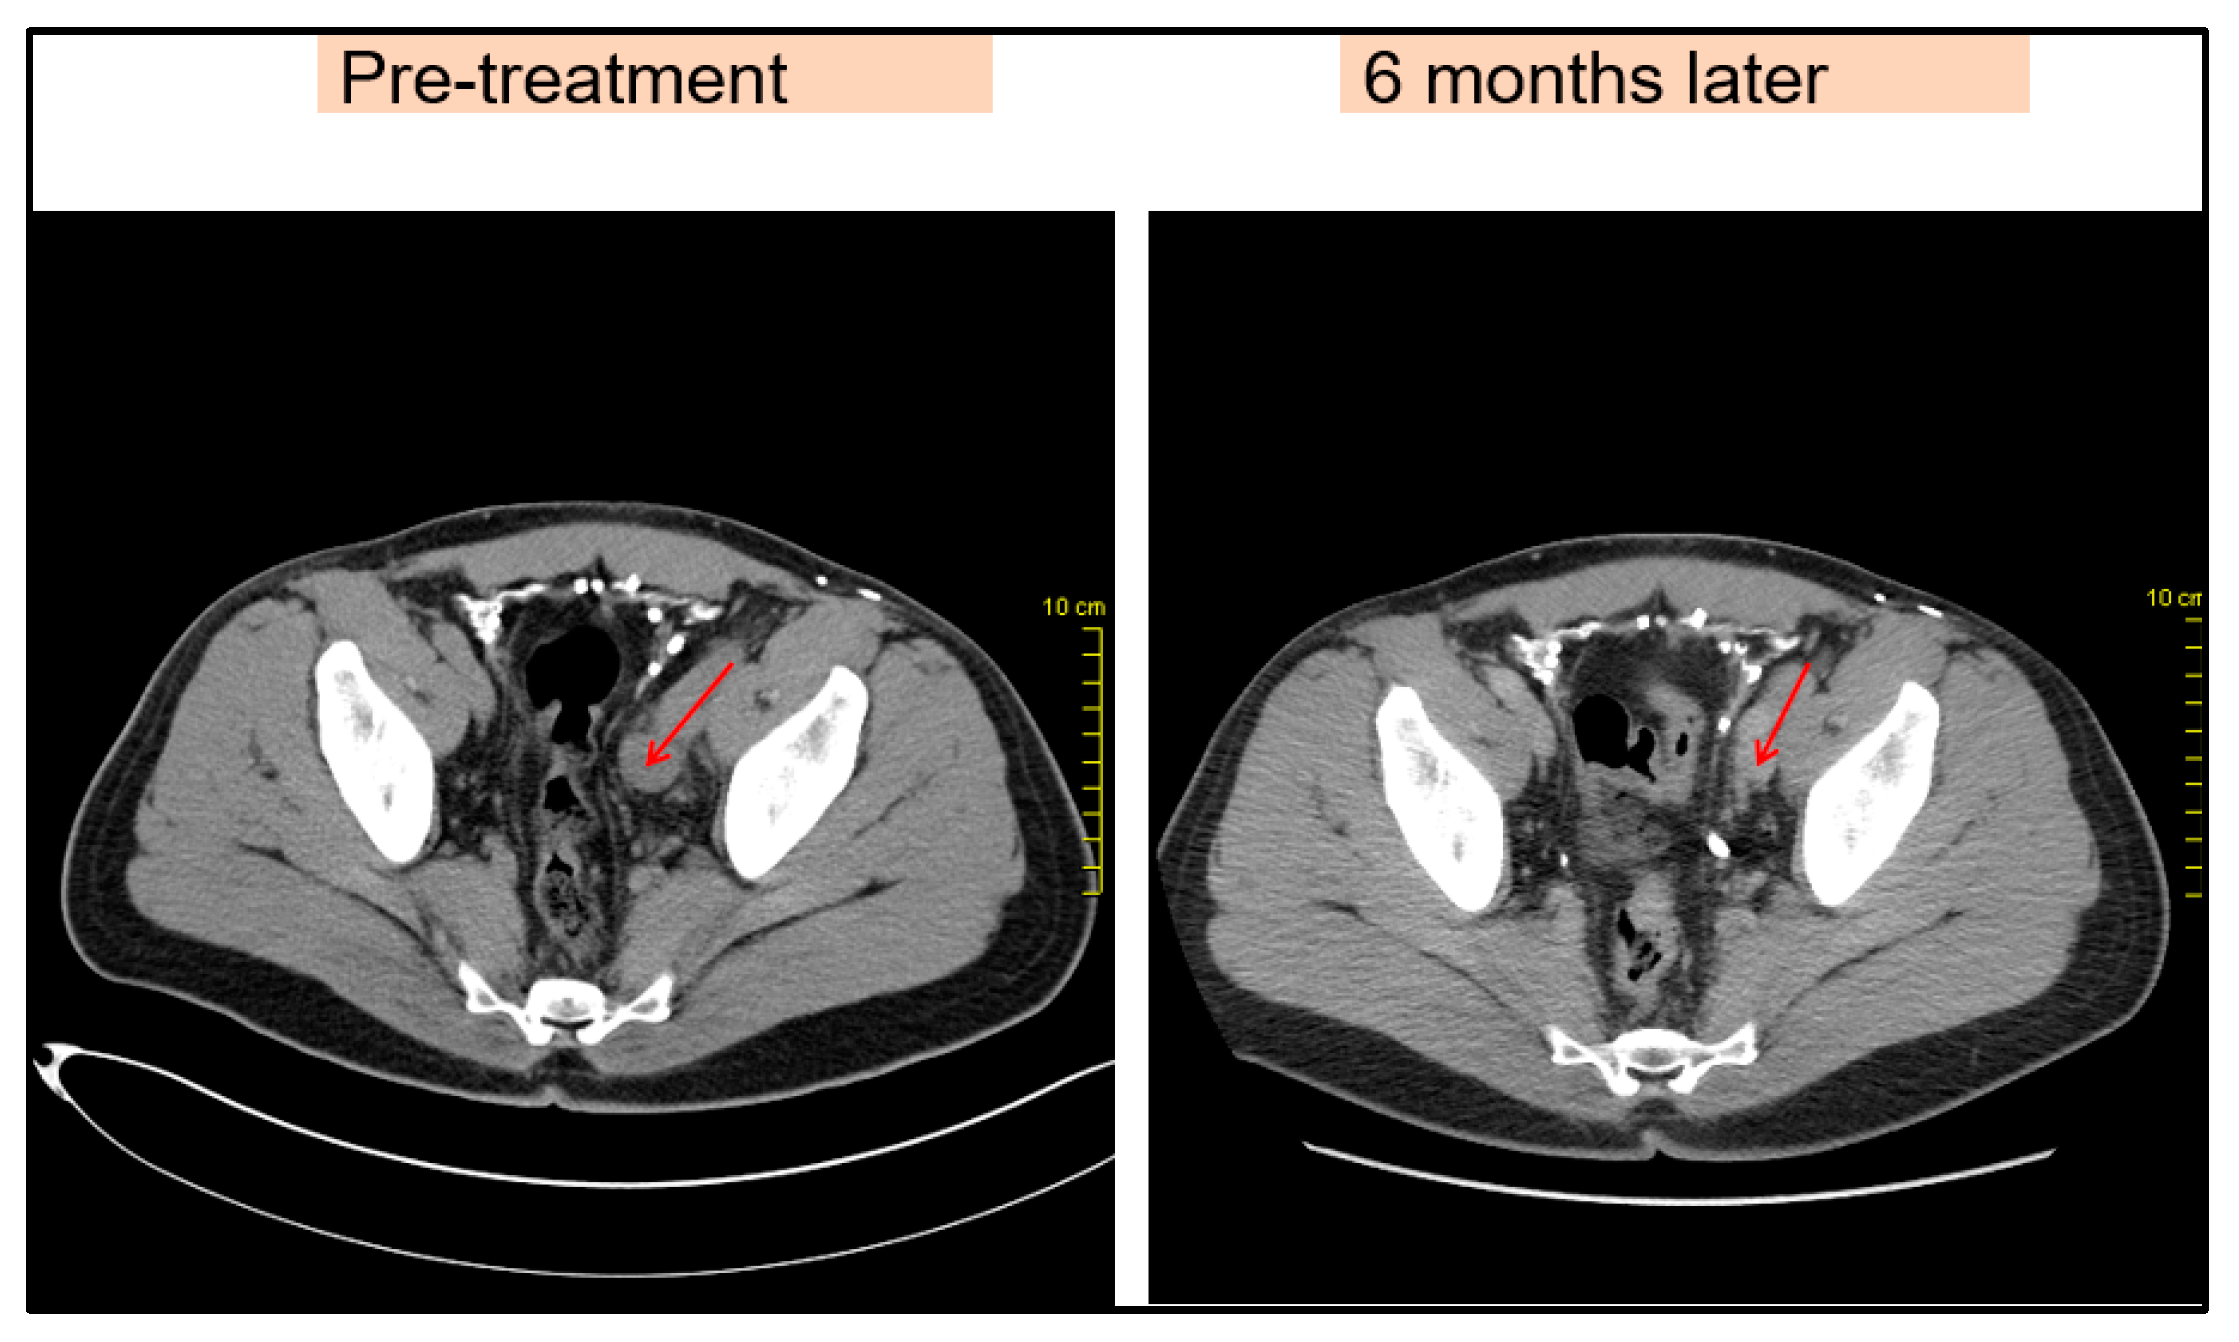

Due to disease progression, in May 2016, the patient started receiving an immunotherapy regimen as follows: Nivolumab 1 mg/kg and Ipilimumab 3 mg/kg every three weeks for four cycles, as well as maintenance immunotherapy with Nivolumab 3 mg/kg every two weeks. The patient responded to this new regimen with a significant regression of the lymph node metastasis, visible on imaging (Figure 3). During immunotherapy, the patient experienced adverse reactions. He presented grade I-II lethargy, grade I myalgia, and grade I-II diarrhea during Nivolumab + Ipilimumab combination therapy. Subsequently, with maintenance monotherapy, the patient developed grade I lethargy, grade I-II skin rash, grade I toxic ophthalmopathy, and hypothyroidism. These toxic effects were treated appropriately. Eye drops and topical corticosteroids were given for ophthalmopathy. Concurrently, the patient was treated with Levothyroxine, 50–75 μg/day. The patient remained in good condition with an excellent performance status (Karnofsky PS = 0) and continued to work during treatment.

Figure 3. Pelvic lymph node metastases before and after immunotherapy, comparison showing regression (red arrow).